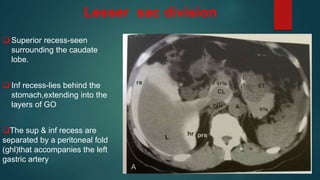

Lesser sac division

 Superior recess-seen

surrounding the caudate

lobe.

 Inf recess-lies behind the

stomach,extending into the

layers of GO

The sup & inf recess are

separated by a peritoneal fold

(ghl)that accompanies the left

gastric artery